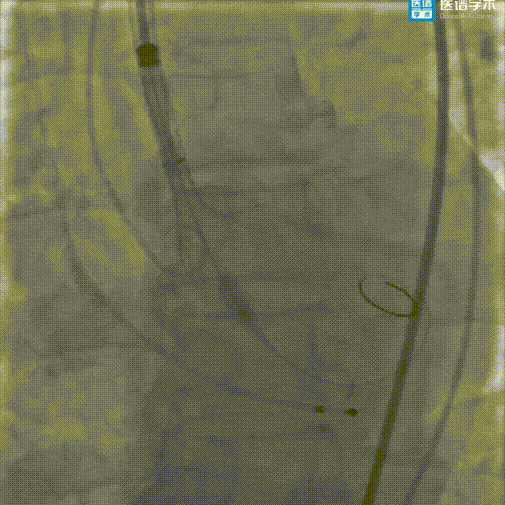

输送器顺利过弓